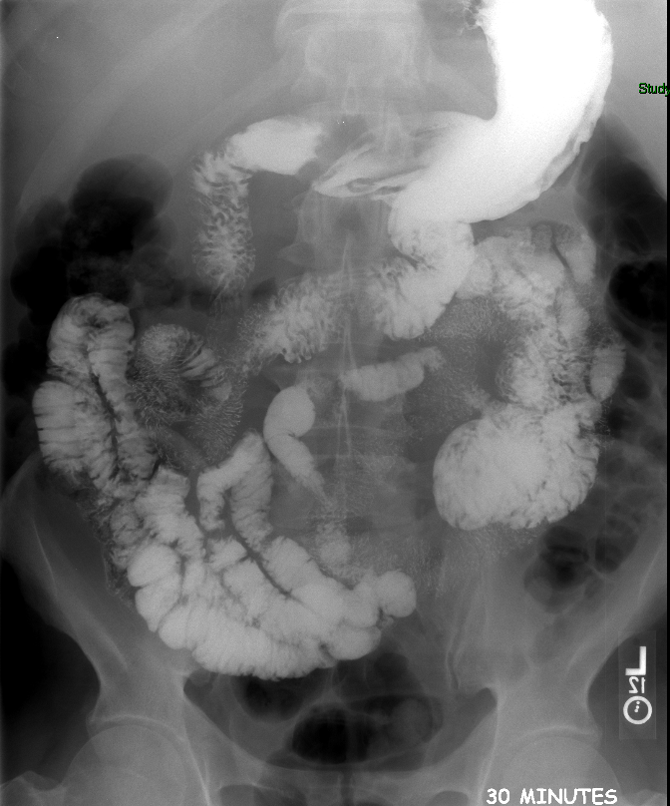

- Once 15 minutes has passed since the patient drank the barium, the technologist will obtain a prone (if possible) radiograph

(key image 2).

- Prone positioning is preferred because while lying prone, the weight of the body provides compression of the bowel loops.

- The film should include the entire stomach as well as the bowel that is filled with contrast.

- The technologist will obtain radiographs at 30, 45, and 60 minutes after the initial administration of barium. If the column of contrast material has not reached the large bowel on the 60 minute film, the technologist will obtain images every 30 minutes until contrast can been seen in the cecum

(key image 3)

(key image 4)

(key image 5).